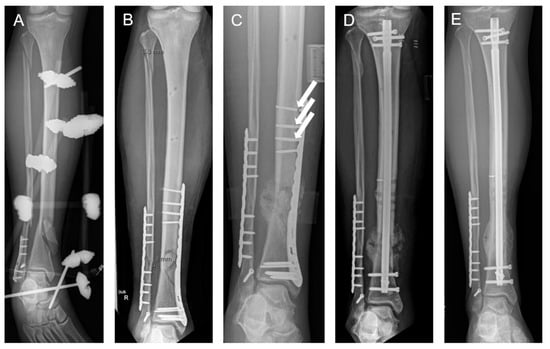

A 12-week longitudinal monitoring study followed a patient who sustained a distal tibial fracture in August 2023 and received fixation with a distal medial tibial locking compression plate (LCP) (Figure 1). In November 2023, the patient returned for biomechanical assessment and underwent initial gait measurements using instrumented insoles and Xsens™ motion capture technology. At that time, the patient reported pain with every step but was walking independently with full weight-bearing and without crutches. In December 2023, surgeons performed a revision surgery, replacing the LCP with an intramedullary nail. Gait measurements began two days after the operation. Over the following 12 weeks, the system recorded the patient’s gait parameters weekly using Xsens™ and instrumented insoles, tracking progress through to full recovery.

Figure 1.

A 29-year-old male patient suffering from a lower leg fracture after a previous and healed ankle fracture in the past (A). The patient was initially treated by plating osteosynthesis of the tibia and fibula (B). At 4 months after surgery, the patient showed an implant failure ((C); arrows) and signs of a hypertrophic non-union as a disturbed bone healing course. After revision surgery (D), the patient underwent a clinically uneventful course and demonstrated full bone healing 6 months post-revision surgery (E).